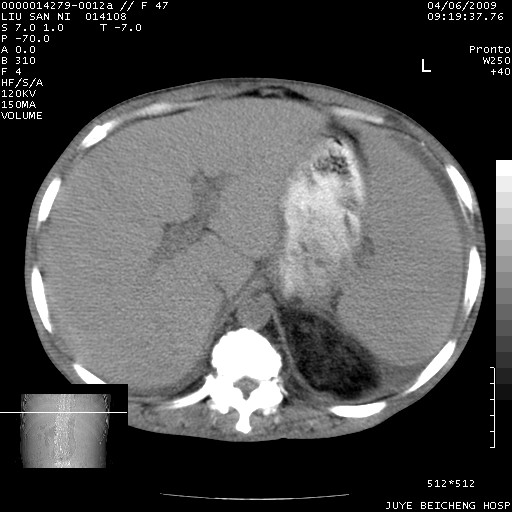

以下是引用前行在2009-4-7 10:31:00的发言:[br]肝脾肿大;双肾增大,双肾盂少量积水可能,肾膜膜增厚,肾周间隙增宽,并见桥间隔,提示结缔组系统疾病、系统性红瘢狼疮肾可能性大。继发右侧胸腔、心包、腹腔积液。

以下是引用深泽交通医院在2009-4-7 11:21:00的发言:[br]双侧肾周密度增高,见条索影,右肾实质见点片状低密度区,考虑弥漫肾炎【自身免疫性?】;;肾性水肿征